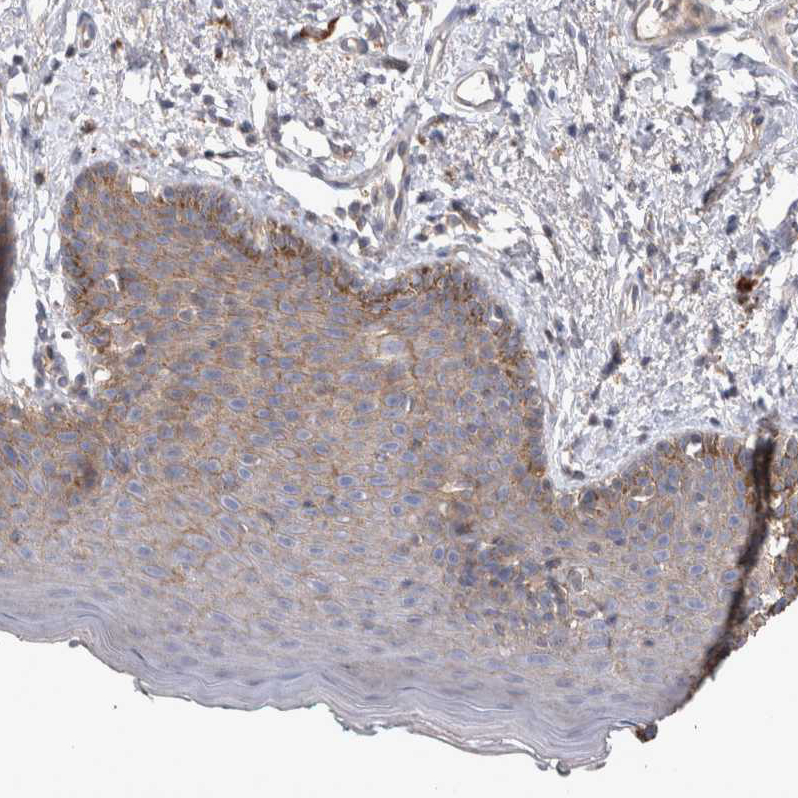

Immunohistochemical staining of human skin shows weak granular cytoplasmic positivity squamous epithelial cells.